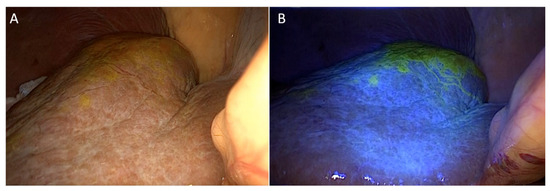

2.1. Detection of Localization under Fluorescent Imaging

- Yoon, S.Y.; Lee, C.M.; Song, T.J.; Han, H.J.; Kim, S. A new fluorescence imaging technique for visualizing hepatobiliary structures using sodium fluorescein: Result of a preclinical study in a rat model. Surg. Endosc. 2018, 32, 2076–2083. [Google Scholar] [CrossRef] [PubMed]

- Chang, Y.W.; Lee, H.Y.; Lee, C.M.; Jung, S.P.; Kim, W.Y.; Woo, S.U.; Lee, J.B.; Son, G.S. Sentinel lymph node detection using fluorescein and blue light-emitting diodes in patients with breast carcinoma: A single-center prospective study. Asian J. Surg. 2020, 43, 220–226. [Google Scholar] [CrossRef]